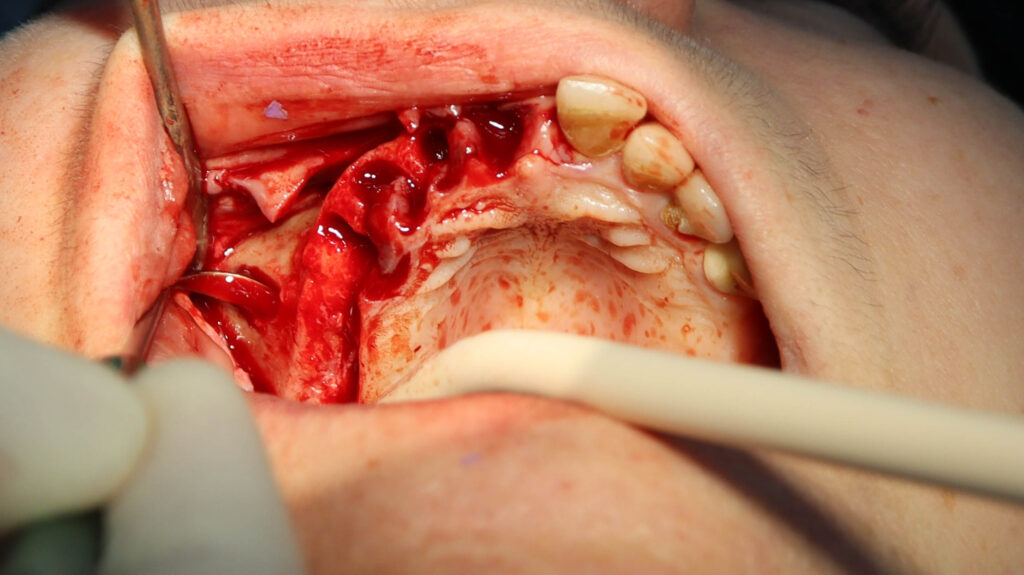

процесс работы

Что было сделано:

На верхней челюсти были удалены зубы, которые находились в неудовлетворительном состоянии, проведена комплексная имплантация по системе All-on-6, установлены 4 имплантата Megagen AnyOne и 2 скуловых имплантата NeoDent.

Фиксации имплантата внутри костной ткани (торк).